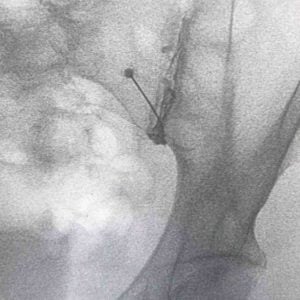

Contraste previo a la infiltración

La infiltración sacroilíaca se puede realizar en quirófano con rayos X o en consulta con nuestro ecógrafo. Sin embargo, es importante que este procedimiento sea realizado por un profesional con experiencia. Además, es fundamental entregar un cuestionario al paciente para evaluar su mejoría en los días o semanas posteriores al procedimiento.